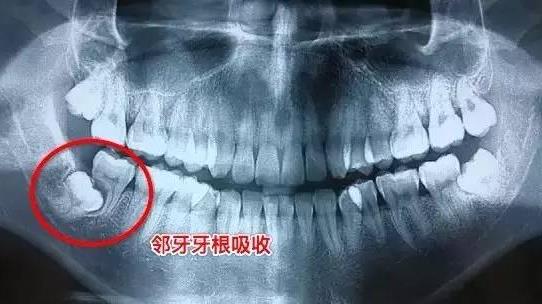

拍牙片在口腔治疗中非常重要。很多时候只有借助牙片,才能对患牙做出正确的诊断,比如牙周的病变、根管的解剖形态、根尖囊肿、智齿危害邻牙等这些情况。

智齿引起的邻牙牙根吸收

在口腔治疗时,常常需要在治疗前、治疗中、治疗后多次拍牙片,确保治疗达到预期效果。千万别因小失大,因为怕辐射不拍牙片啊。

智齿可以引起牙根吸收,废掉你智齿的第二磨牙。智齿牙骨质增生,可以引起牙根肥大,拔的越晚,可能越不好拔。